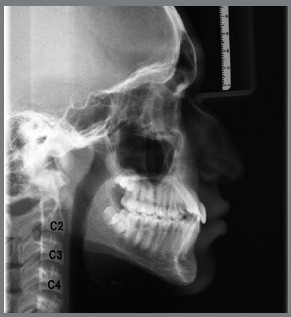

Material and methods: A total of 148 lateral cephalograms (78 males, 70 females) of Class II malocclusion patients, and 60 lateral cephalograms (30 males, 30 females) of normal occlusion patients were included. The following linear cephalometric measurements were performed: Co-Gn (effective mandibular length), Co-Go (ramus height), and Go-Gn (length of mandibular body). Mean values of increments between stages (I-A, A-T, I-T) were obtained for each group and gender. Results were compared using the Student t-test, and a significance level of 0.05% was adopted.

Abstract Image